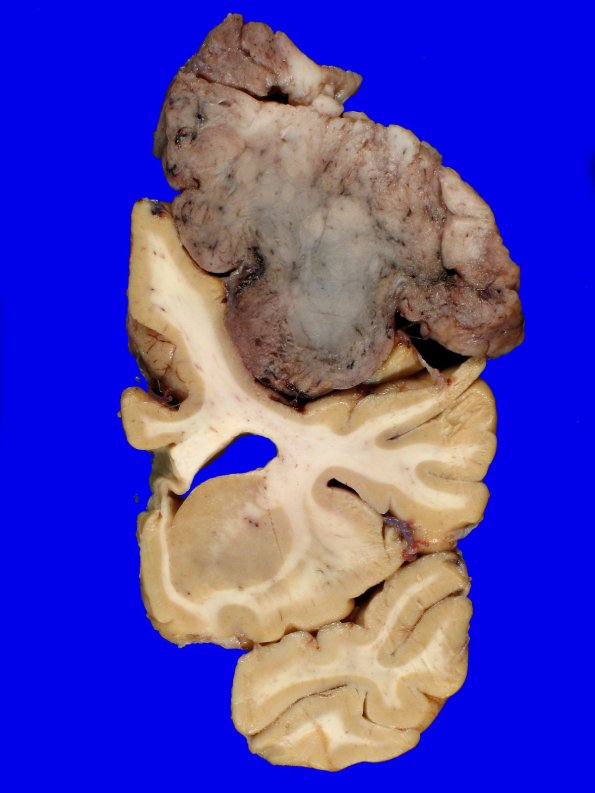

Washington University Experience | NEOPLASMS (MENINGIOMA) | Gross Pathology | 72D6 NCL (Case 72) Gross_16

Additional images of the tumor relationship with the brain.